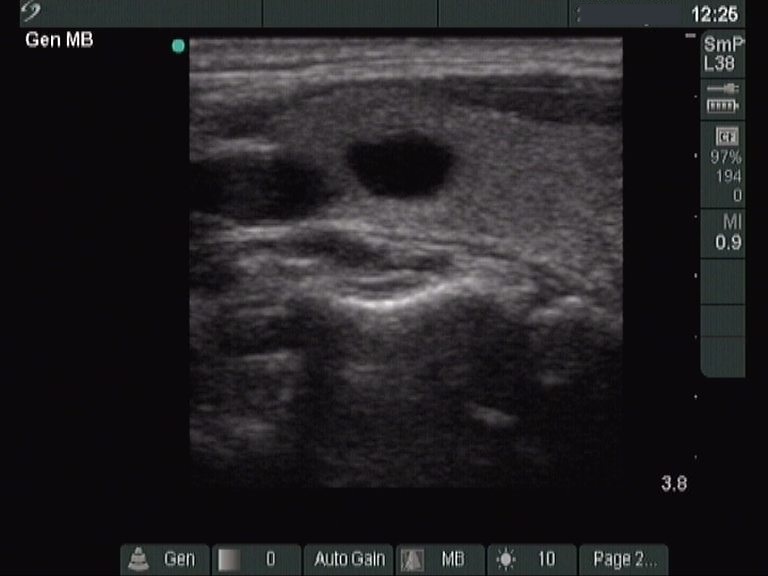

Transverse scan |

According to the EU-TIRADS, this lesion cannot be regarded as a purely cystic nodule due to the presence of wall-thickening (yellow arrows). The EU-TIRADS defines this lesion as an EU-TIRADS 3 nodule.